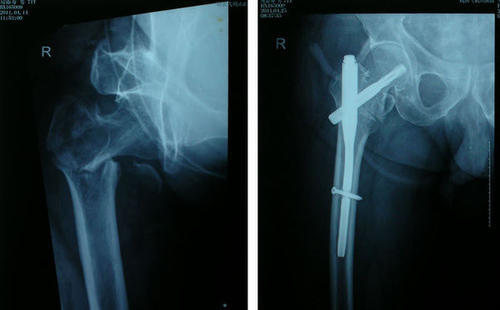

68岁阚先生,身体还算可以,虽然也有高血压,高血脂,但是药物控制的一直还算不错。阚先生也比较注重健康,每天坚持锻炼,这天早晨锻炼,由于刚刚下过雨,路面湿滑。阚先生不小心摔了一跤,送医后发现是髋部骨折。经过医生的评估,建议老人手术治疗,但是家人感觉这么大岁数了,手术治疗怕老爷子受罪,最后还是坚持保守治疗,可是在一年后,老人家却撒手人寰。为什么这个骨折这么致命呢?

四、手术治疗还是保守治疗?

一般情况下,髋部骨折强烈建议积极进行手术治疗,这样可以尽快的缓解患者的痛苦,及早的自由活动,减少并发症的发生,研究发现,髋部骨折患者,绝大部分不是因为骨折本身去世,而是因为各种并发症。

但是手术治疗适合每一个人吗?不是的,对于一些基础疾病多,身体极度虚弱,不能耐受手术的患者只能保守治疗。